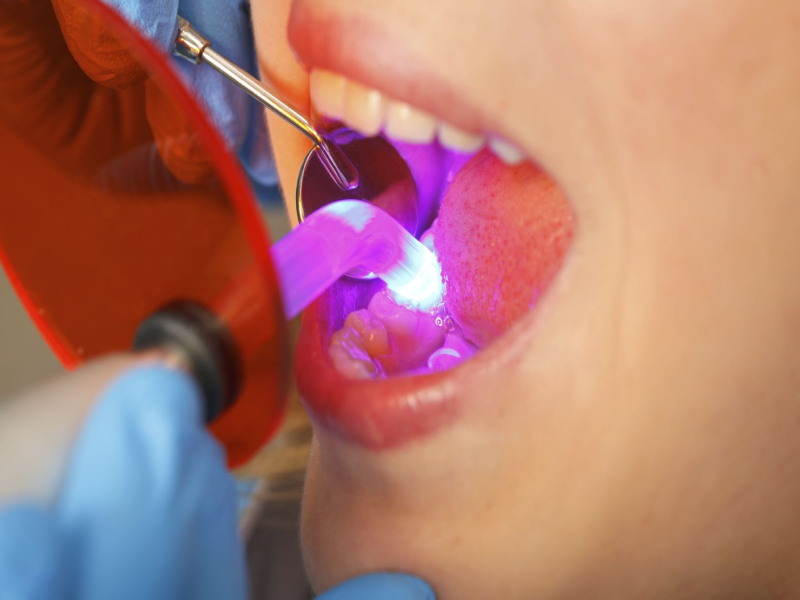

Utilisation de Bis-Acryl

- Mélange avec le mélangeur de pistolets spécial

- Mettre sur le moule de la dent

- Attendre pour qu'il devienne dur (environ 2 à 5 minutes)

- Lisse les bords à l'aide d'outils spéciaux

- Polonais pour le faire briller

Matériaux pour couronnes provisoires : Nouveautés en 2024

La dernière nouveauté est Impression 3D. Les médecins peuvent désormais :

- Scanner votre bouche avec un petit appareil photo

- Conception votre couronne sur un ordinateur

- Imprimer en 30 minutes seulement

Ces couronnes s'adaptent très bien et sont belles. Elles coûtent plus cher mais permettent de gagner du temps.